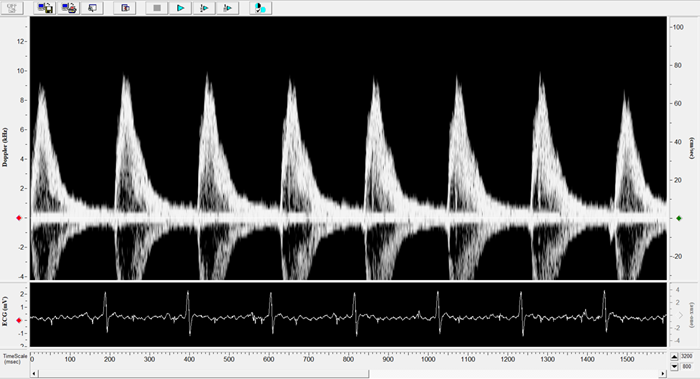

Carotid

Carotid Image. Image Credit: Scintica Instrumentation Inc.